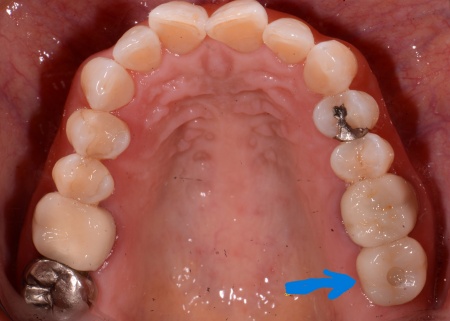

拝見したところ、左上の一番奥の歯(第2大臼歯)には金属の被せ物が装着されていました。

その後、歯ぐきやあごの骨が回復するまで一定期間待ち、インプラントが骨としっかり結合しているかを確認しました。

問題がないことを確認したうえで歯の型取りを行い、インプラントの上に装着する人工歯を作製しています。

最後に完成した人工歯を取り付け、噛み合わせに問題がないかなどを確認し治療を終了しました。